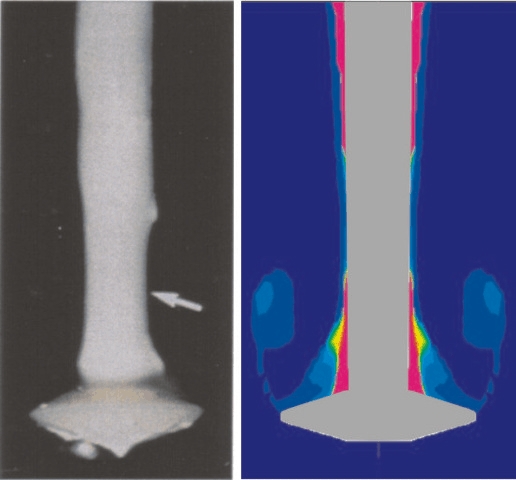

Verweilzeiteinfluss auf experimentelle und numerische Thrombenablagerung

Thrombenwachstum an einem Stent